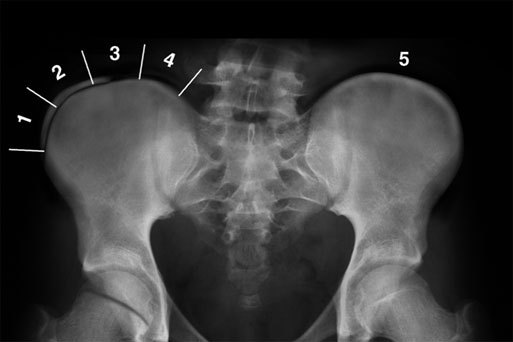

Степень взросления определяется по окостенению тазовых костей по методике, которую описал Joseph Risser. Считается, что 3 степень – самое оптимальное время для операции при наличии показаний. Человек уже не будет активно расти, но позвоночник и спинной мозг достаточно эластичные и смогут без всяких последствий перенести коррекцию даже больших деформаций. Примерный возраст 13-15 лет.

Можно сказать, что у детей и подростков уже само искривление позвоночника IV степени является показанием к оперативной коррекции деформации позвоночного столба. Одна известно, что в большинстве случаев при такой тяжелой степени деформации хирургические вмешательства оказывают весьма паллиативными, поскольку улучшаются только показатели функции внешнего дыхания, а гипертензия в малом круге кровообращения часто сохраняется. Отсюда следует, что необходимо оперировать больных до того, как у них разовьется искривление позвоночника IV степени. К сожалению, это не всегда возможно, так как больные часто обращаются к ортопеду слишком поздно. При установлении показаний к хирургическому лечению необходимо основываться на рентгенологических признаках возможного прогрессирования заболевания, к которым, как мы уже указывали, относятся: отставание локального костного возраста позвоночника от паспортного, наличие I-II степени патологической перестройки межпозвонковых дисков на ранних стадиях развития сколиотической деформации, отсутствие оссификации апофизов гребней подвздошной кости, остеопороз позвонков на вершине искривления. Большое значение имеет динамическое наблюдение за течением заболевания. Использование перечисленных рентгенологических признаков в сочетании с данными клинического обследования позволяет прогнозировать течение сколиоза и выбрать наиболее рациональный метод лечения.